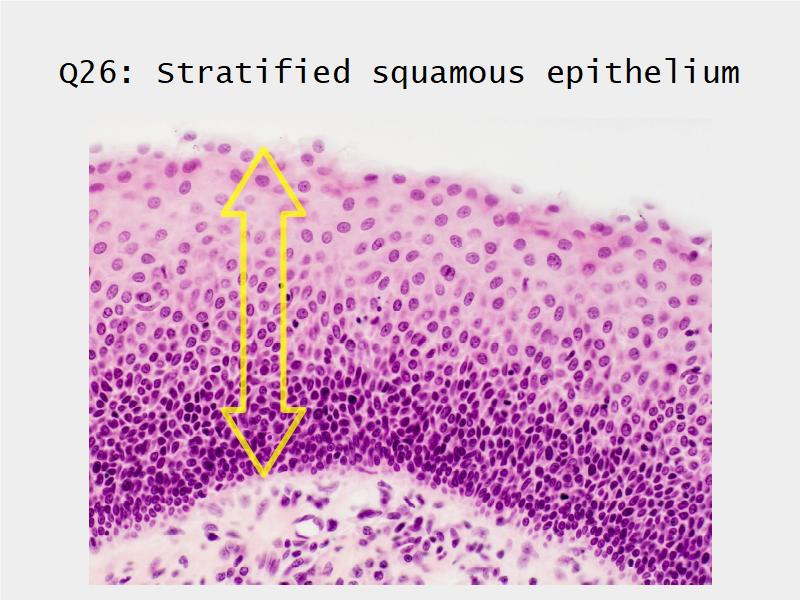

Respiratory epithelium

- Pseudostratified

- Ciliated

- Columnar

- Epithelium with

- 4 Cells

- Ciliated columnar cells

- Non-ciliated columnar cells

- Goblet cells

- Basal cells